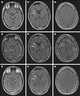

Biotin deficiency

Biotin deficiency is a nutritional disorder which can become serious, even fatal, if allowed to progress untreated. It can occur in people of any age, ancestry, or gender. [Source: Wikipedia ]